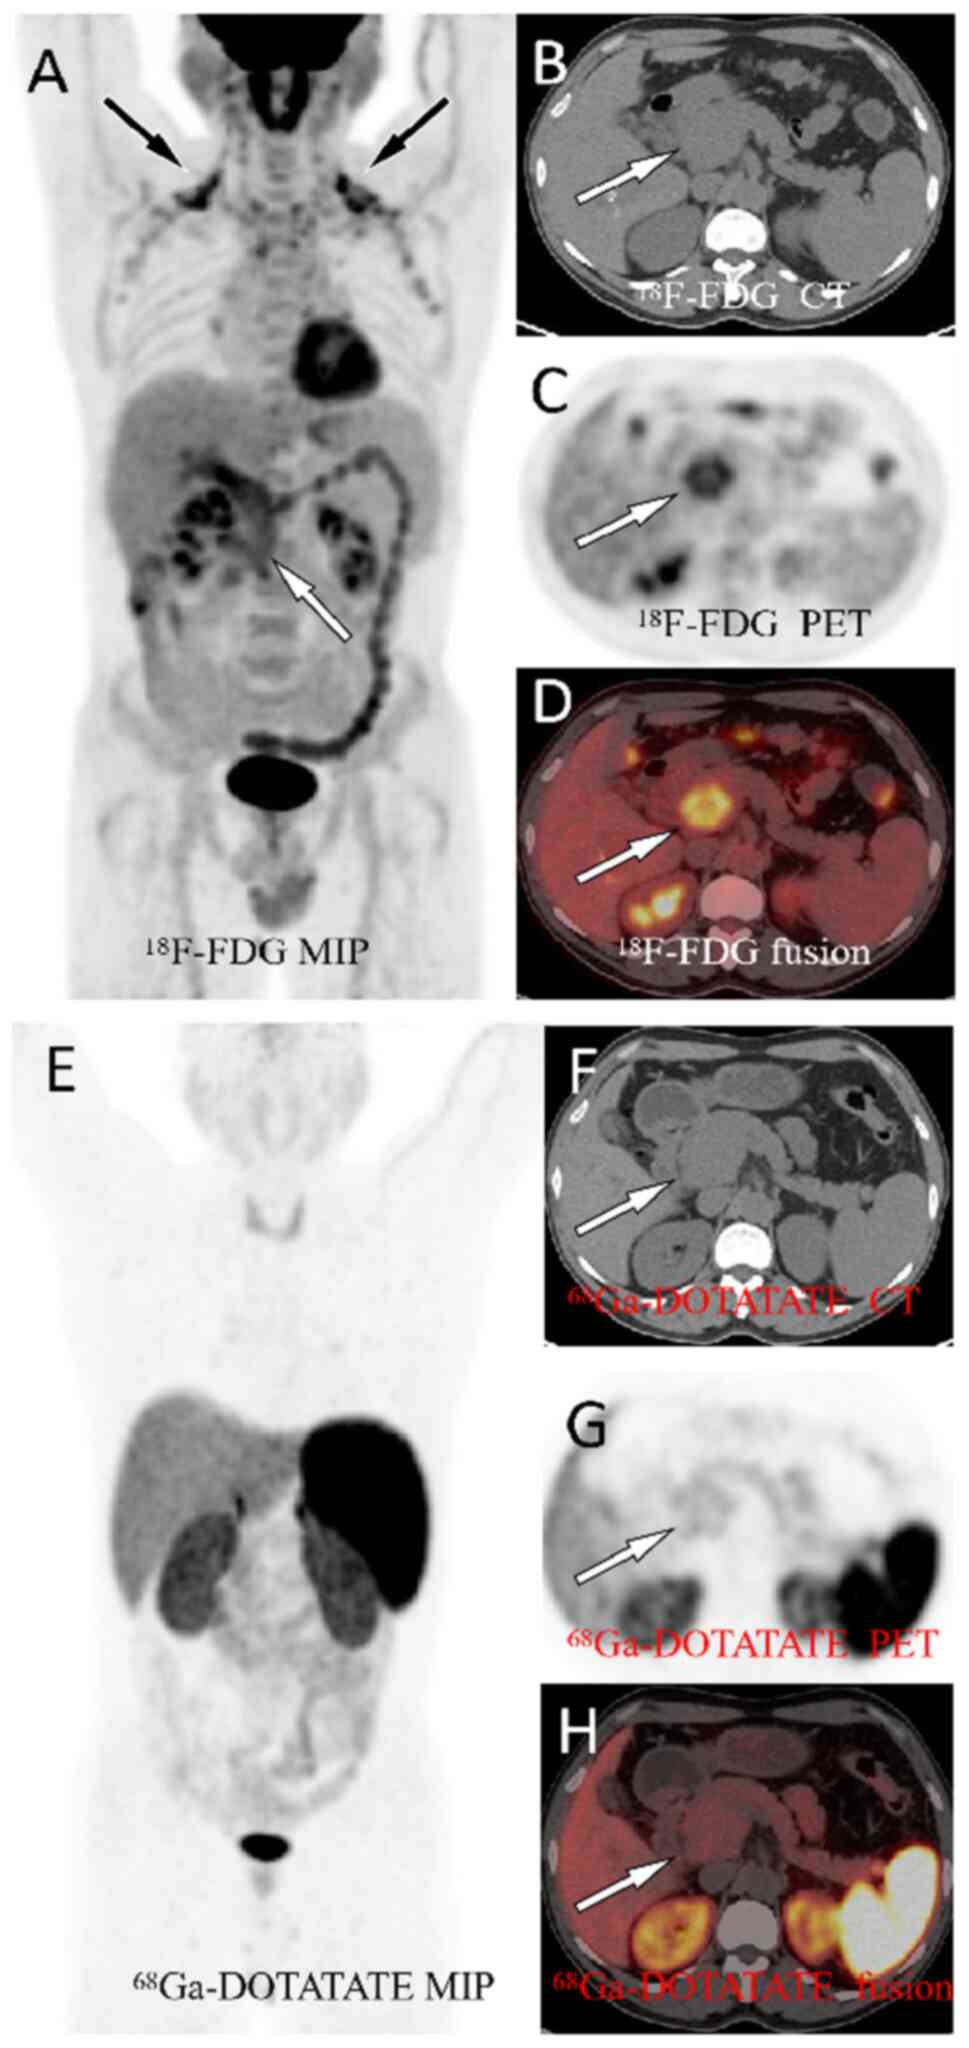

Nesidioblastosis is a rare cause of hyperinsulinemic hypoglycemia in adults and its clinical features are similar to those of insulinoma with recurrent hypoglycemic attacks. The present study reports the case of a 48‑year‑old man who visited the Affiliated Hospital of Zunyi Medical University (Zunyi, China) with a 5‑year history of recurrent hypoglycemic symptoms such as dizziness and palpitations. Abdominal magnetic resonance imaging (MRI) showed a mass of ~1.2x1.0 cm in the head of the pancreas, which was suspected to be an insulinoma. For confirmation, the patient underwent both fluorine‑18‑fluorodeoxyglucose (18F‑FDG) and gallium‑68‑labeled 1,4,7,10‑tetraazacyclododecane‑1,4,7,10‑teraacetic acid‑d‑Phel‑Tyr3‑Thr8‑OC (68Ga‑DOTATATE) positron emission tomography/computed tomography (PET/CT), which showed a moderately increased uptake of 18F‑FDG but no uptake of 68Ga‑DOTATATE in the corresponding lesion. The patient subsequently underwent surgery to remove the lesion, which was pathologically confirmed as a pancreatic nesidioblastosis. This case showed that nesidioblastosis should be considered a differential diagnosis for insulinoma and that dual nuclear tracer PET/CT imaging is helpful for differentiating between the two. If conventional imaging techniques such as ultrasound, CT and MRI cannot identify the cause of hypoglycemia in future cases, dual‑nuclide tracer PET/CT imaging should be considered.

Hu X, Li D, Wang R, Wang P and Cai J: Comparison of the application of 18F-FDG and 68Ga-DOTATATE PET/CT in neuroendocrine tumors: A retrospective study. Medicine (Baltimore). 102(e33726)2023.PubMed/NCBI View Article : Google Scholar